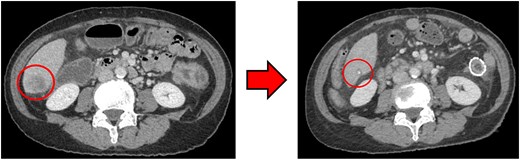

Computed tomography (CT) revealed wall thickening of the descending colon with increased pericolic fat tissue density (Fig. 2). Multiple enlarged regional lymph nodes were observed. Liver metastases were identified in the liver S5/7 and S6 (Figs 3 and 4). The S5/7 lesion was located near the anterior branch of the portal vein and the right hepatic vein.

(Left: Before NAC) Liver metastasis in the liver S5/7. It was located near the anterior branch of the portal vein and the right hepatic vein. (Right: After NAC) Liver metastasis in the liver S5/7. Complete resolution of the S5/7 liver metastasis.

After four cycles, CT revealed significant shrinkage of the primary lesion (Fig. 2), disappearance of lymph node metastases, and complete resolution of the S5/7 liver metastasis (Fig. 3). The S6 lesion had decreased substantially, with near-complete necrosis (Fig. 4). Tumor markers declined (CEA 16.7 ng/mL, CA19–9 31.1 U/mL).